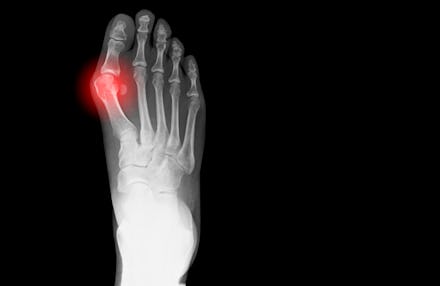

A bunion is a bony bump formed near the point where the big toe meets the first metatarsal bone — one of the five long bones that stretch the length of the foot. It's formed when the first metatarsal bone pushes out on the big toe, forcing it into a diagonal direction. "It causes pain and inflammation around it," Loi wrote in an email.

The same thing can happen on the other side of the foot, where the fifth metatarsal bone meets the pinky toe. "It's called the bunionette," Loi said.